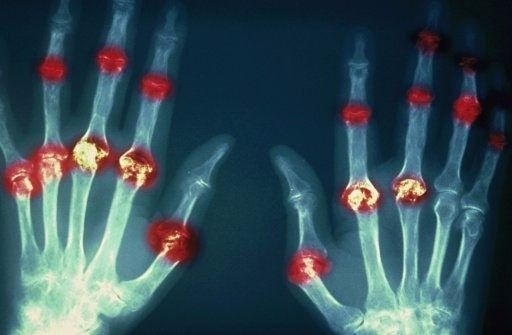

?類風濕關節炎

類風濕關節炎是一種高度致殘的自身免疫性疾病,發病十年的患者中至少有50%的人失去勞動能力。

類風濕關節炎©Health Same of Flickr

1977年,Baldwin在用骨髓干細胞移植治療再生障礙性貧血的過程中,意外發現患者的類風濕關節炎得到緩解。

2004年,歐洲骨髓移植和抗風濕病聯盟對60例類風濕病關節炎移植患者進行回顧性分析,這些患者的關節破壞都達到不可修復程度,生活不能自理,通過干細胞移植治療后,67%的患者得到明顯緩解。

我國國內多家醫院已開展了干細胞治療類風濕性關節炎的臨床研究。首例自體干細胞移植治療類風濕關節炎在北京協和醫院完成。經過5個月隨訪,這些經常規藥物治療失敗且病情發展迅速的患者,在接受干細胞移植治療后,癥狀均獲得改善,關節腫脹消失,各項檢查指標恢復正常。

解放軍323醫院2011年的一項臨床研究中,27位患者(對照組)只使用藥物治療;另外153位患者(細胞治療組)在藥物治療的基礎上進行臍帶間充質干細胞輸注。結果顯示,治療組DAS28、HAQ 評分、ACR20較對照組下降明顯(分值越低,療效越好),Th1/Th2趨于平衡、Treg升高與臨床實驗指標及癥狀的緩解直接相關。